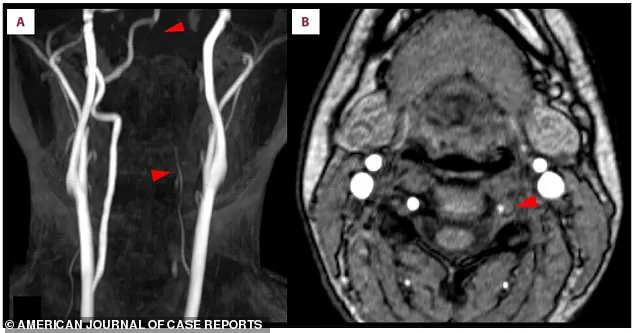

These bright spots, visible as arrows in Panel A of the scan, were the telltale signs of a lack of blood flow.

Further analysis of the posterior cerebral artery, shown in Panel B, revealed a missing section of the normally smooth arterial wall—a blockage that had severed the lifeblood to critical brain regions.

The scans also highlighted a faint, almost broken appearance of the left vertebral artery, a key blood vessel in the neck.